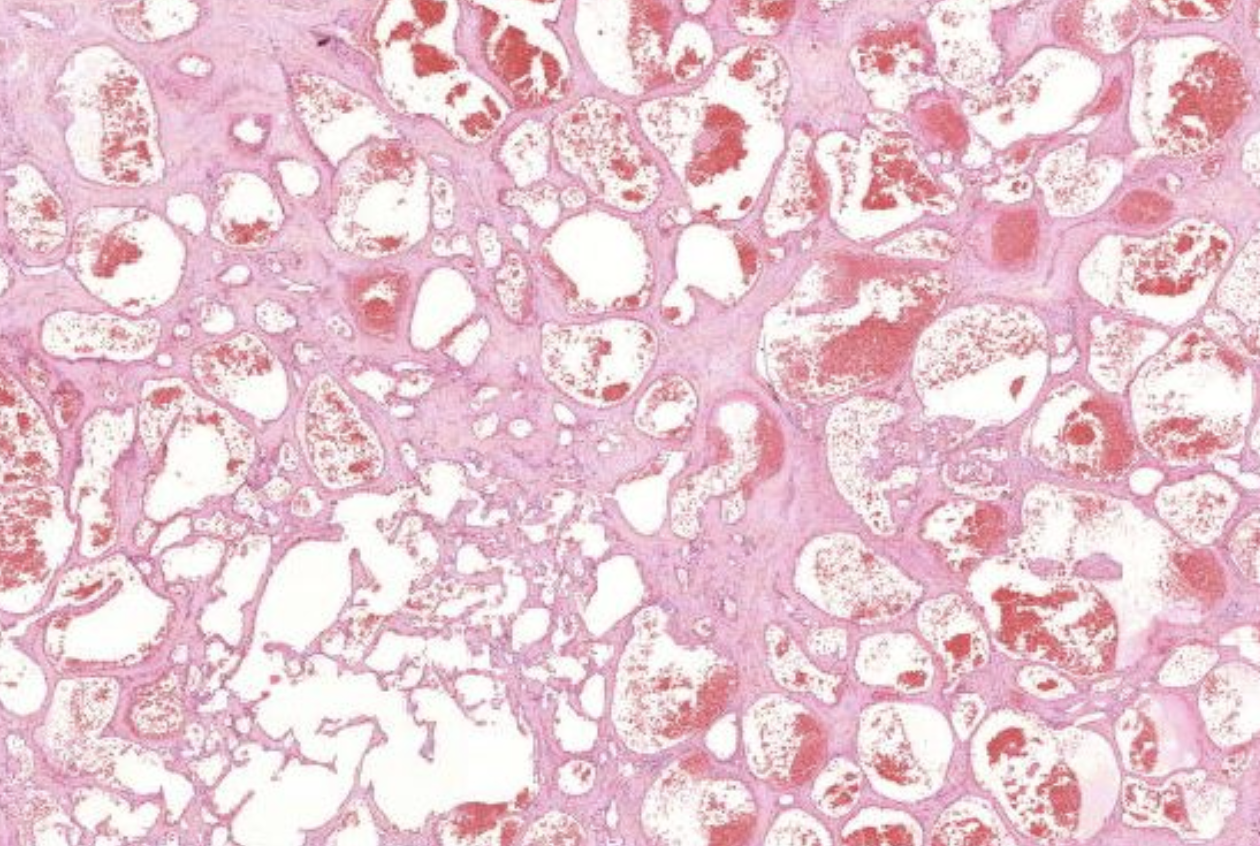

40) WElches Präperat ist hier zu sehen?

Histopathologisches Bild: Kolonschleimhaut

Kavernöses Hämangiom.

Es zeigen sich unterchiedlich weite Blutgefäße und darin ganz viele Erythrozyten.

Wenn diese Gefäße super groß werden, dann nennt man die Kavernös. Vaskuläre tumoren sind in der Leber recht häufig

40) Was könnte eine komplikation der kavernen im Kavernösen Hämangiom sein?

Thrombosieren der Kavernen und Nekrosen darin.